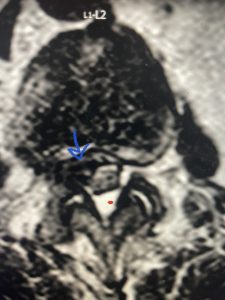

The next patient is a 71 year-old male with a two-year history of low back pain and lower extremity pain, numbness and weakness. His left leg was worse than the right. He had had five epidurals with no improvement. He also had tried physical therapy and medicines but nothing helped. He also felt that over the last three weeks he had gotten worse. He also had recently had some decreased sensation of bladder fullness and difficulty with bowel movements. MRI revealed a very tight L2-5 stenosis with an extruded L3-4 disc fragment (Fig 3).

(Figs 3a) Sagittal (a) and Axial (b) T2-weighted lumbar MRI demonstrating severe spinal stenosis L2-5 (arrow)and extruded disc at L3-4 on axial image (arrow)

(Fig 3b)

He had concentric severe stenosis with severe compression of the lateral recess and foramen at L3-4 secondary to the superimposed disc herniation. The fact that he had gotten worse with subtle cauda equina features with an extremely tight canal, he underwent a decompressive laminectomy. We also augmented his laminectomy with an in situ fusion from L3-5 as he was relatively young, with more time to reform arthritis, and had been unstable enough to extrude a disc fragment. By placing “bone dust” or bone material along the sides of the spine, specifically laying it across the transverse processes after they have been drilled to bleeding bone, you provide an environment where bone formation is induced to connect the segments, stabilize them, and thereby reduce the signal to make more arthritis as that signal is still present despite the laminectomy. What was interesting was that we encountered a large extruded disk fragment that was significantly contributing to his compression which is often not found in patients in this age bracket. Post operatively he had much improvement of leg pain.